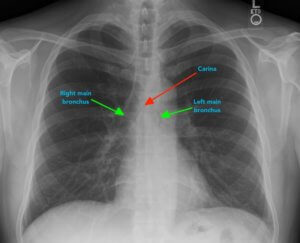

Рентген легенів

В якості основного діагностичного методу використовується рентгеноскопія легень. За допомогою такої процедури можна виявити вогнище запалення, оцінити розмір вражений області, визначити форму захворювання.